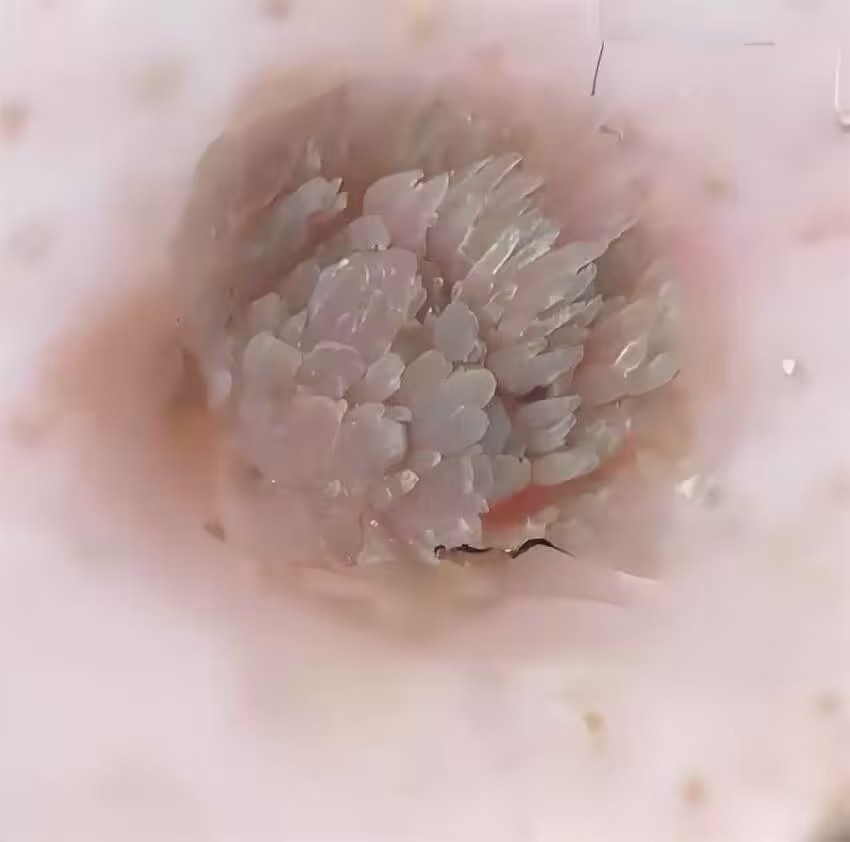

所有人都倒吸一口涼氣——內部竟是密密麻麻的黑色絲狀物,像極了腐爛的菜花莖稈。

「這是典型的傳染性軟疣合併真菌感染!」主治醫師王主任面色驟變,「您最近是不是住過酒店?」